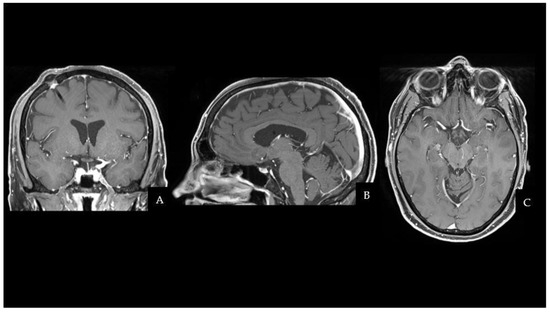

The patient fully recovered after the procedure and had no neurological complications. Even though the histopathological characteristics were different from the previous testicular NGGCT, the morphologic and immunophenotypic examination confirmed the lesion to be a mixed GCT (Oct4+, SALL4+, CD117+; Ki67≃ 10%). One month after surgery, the patient started two cycles of cisplatin, etoposide, and ifosfamide (PEI) chemotherapy, followed by 18 sessions of conventional radiation therapy (CRT). MRI scans at 3 and 6 months after the end of treatment did not document disease recurrence. The two-year follow-up brain MRI is shown in Figure 2 and has not demonstrated any sign of regrowth in the surgical field. Apart from permanent Diabetes Insipidus, the patient does not present any endocrine disorders or neurological sequelae. Despite medical advice, the patient and his family did not undergo any genetic analysis to investigate cancer predisposition syndromes.

Figure 2. Two years later, a CE-T1W MRI scan showed no evidence of residue or recurrence of the disease in the suprasellar region. (A) Coronal sequence. (B) Sagittal sequence. (C) Axial sequence. Abbreviations: contrast-enhanced T1W (CE-T1W); magnetic resonance imaging (MRI).